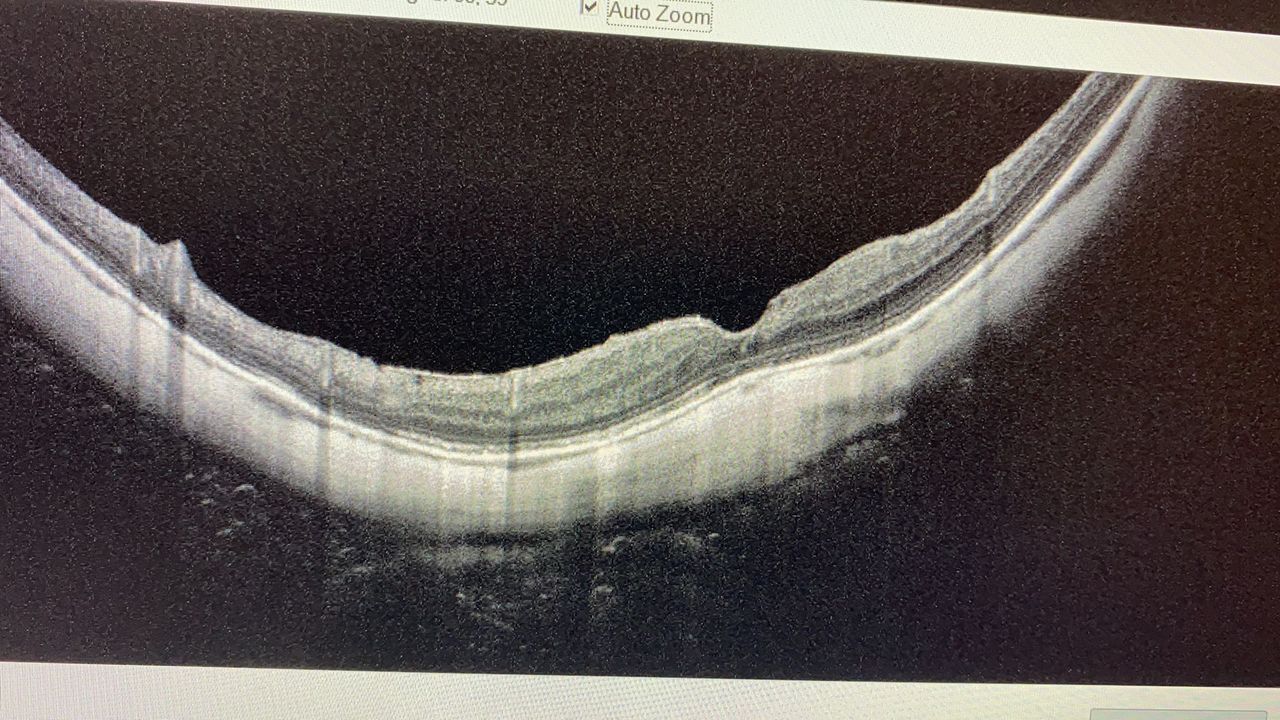

Le maculopatie sono il mio campo di interesse clinico e scientifico sia per quello che concerne la Diagnostica che la terapia con iniezioni intravitreali

I pazienti affetti da patologie retiniche come retinopatia diabetica, occlusioni vascolari o degenerazioni maculari legate all’età, dopo attenta valutazione oftalmoscopica e mediante esame OCT vengono indirizzati e sottoposti ai diversi trattamenti terapeutici. Lo studio si avvale di Argon laser per i trattamenti di pazienti affetti da retinopatia diabetica o occlusioni vascolari.

Mi occupo soprattutto della diagnostica per Immagini con OCT, ANGIO OCT e fluorangiografica ,della terapia laser delle malattie retiniche e del trattamento con farmaci ad iniezione intravitreale.